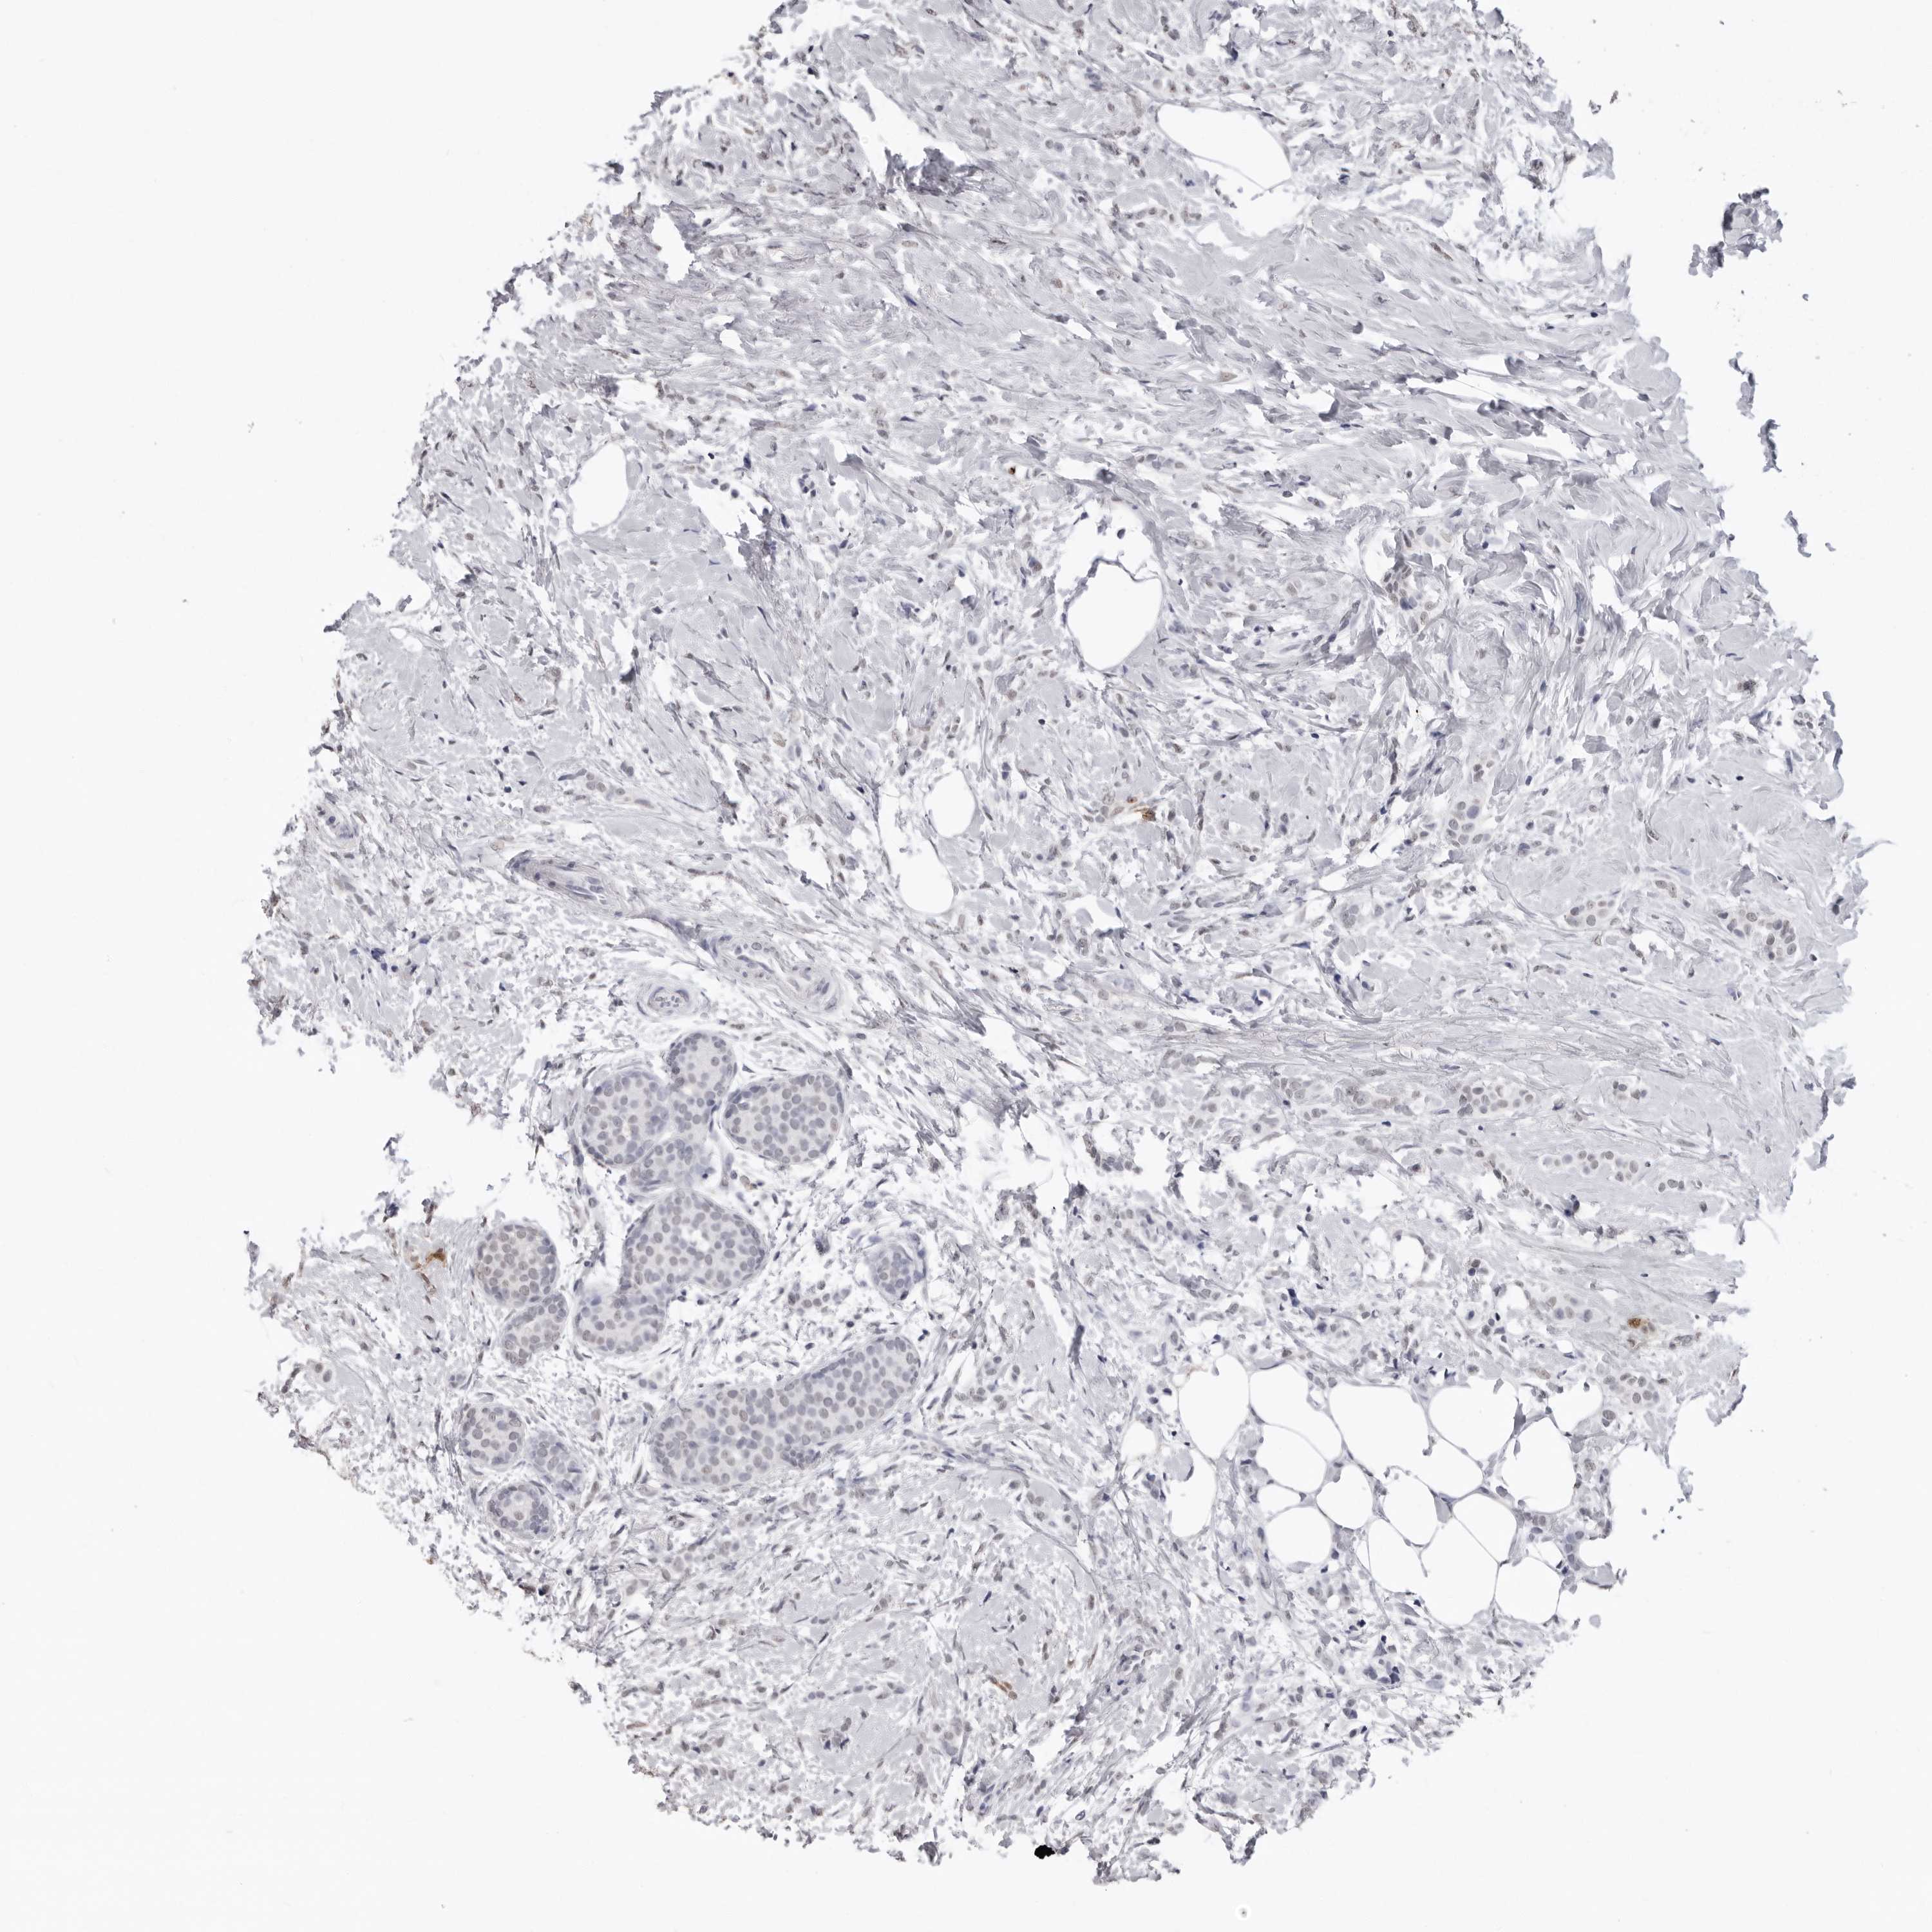

CANCER BREAST CANCER Show tissue menu

BRCA TCGA BRCA VALIDATION PROTEIN EXPRESSION